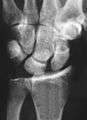

Stress view showing scapholunate instability